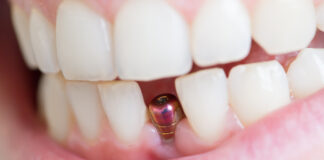

Mantenimento del profilo tissutale nell’impianto post-estrattivo ritardato: obiettivo realistico?

Gestione chirurgico-protesica di un sito implantare post-estrattivo, con focus sulla gestione del profilo tissutale nell’impianto post-estrattivo mediante il restauro provvisorio, utilizzato come supporto per...